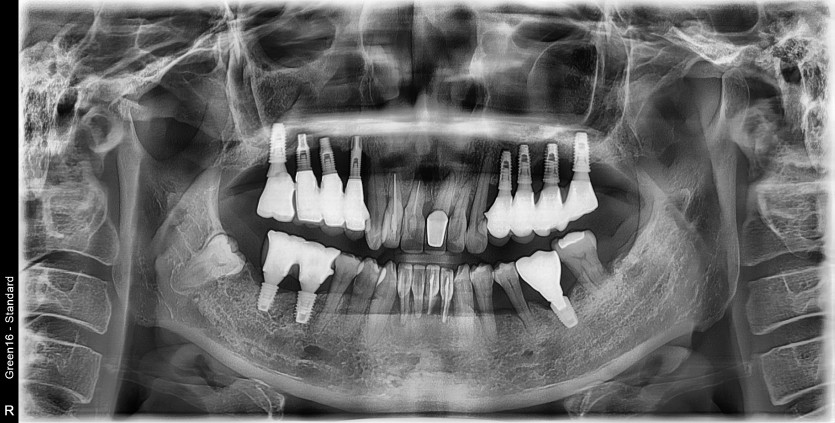

#14.15.16.17 타원 임플란트 제거 후

임플란트 식립+ 치조골 이식술 시행하였습니다.